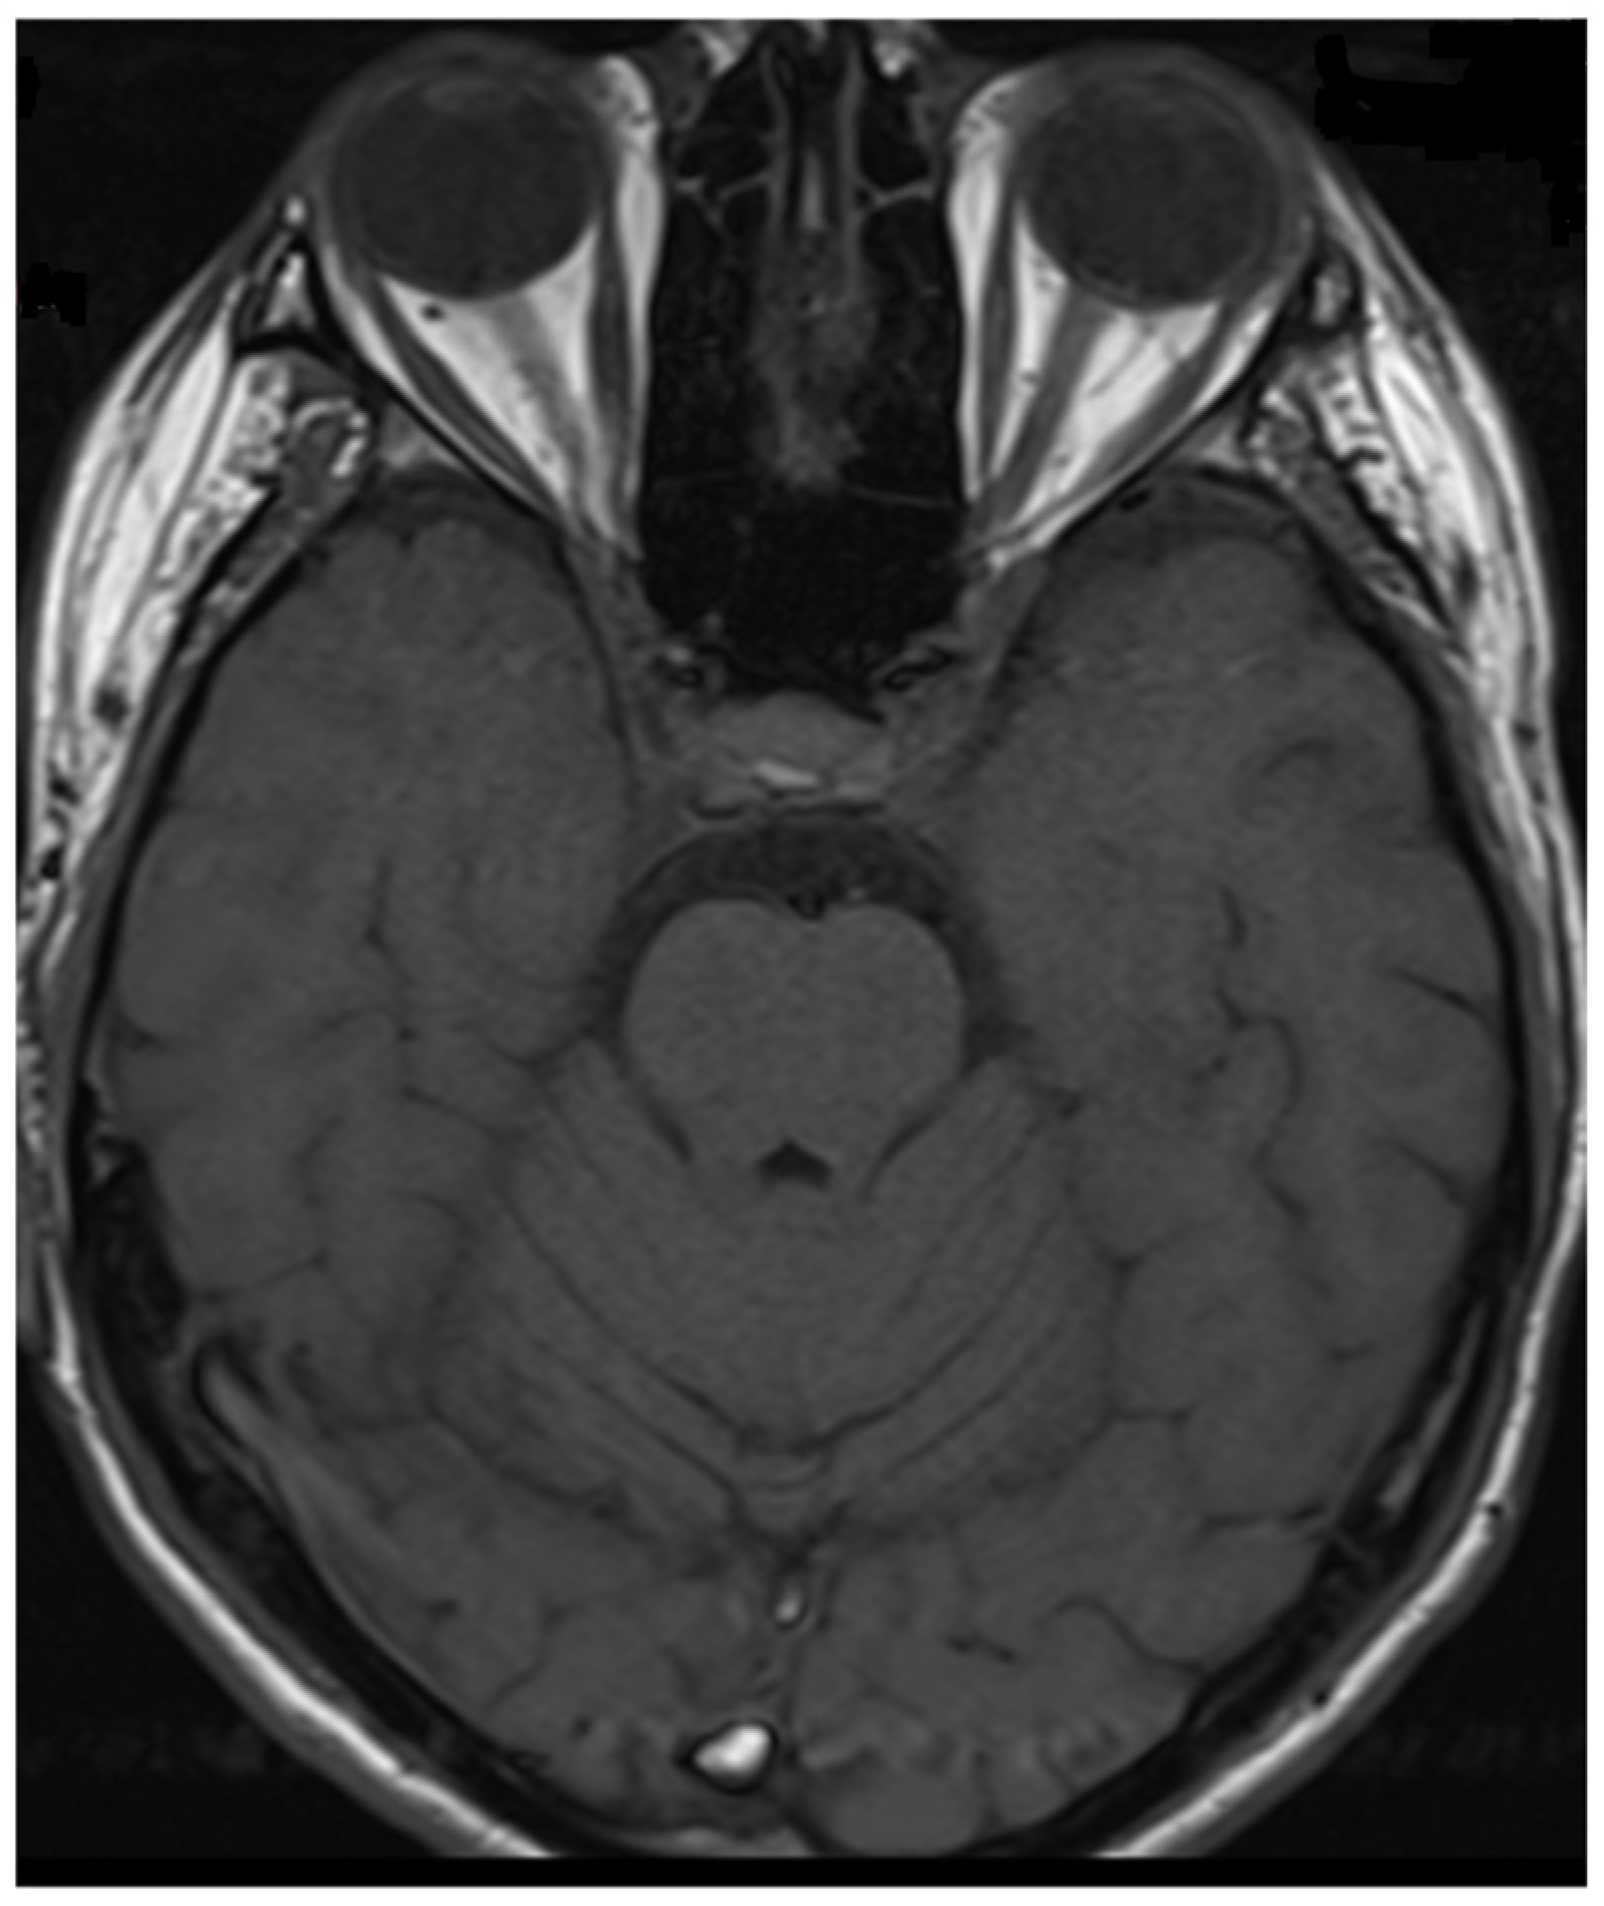

| Brain, brainstem or cerebellar syndrome | multiple ill-defined T2-hyperintense lesions in supratentorial and often infratentorial white matter, deep gray matter involvement, ill-defined T2-hyperintensity involving pons, middle cerebellar peduncle, or medulla, cortical lesion with /without lesional and overlying meningeal enhancement |